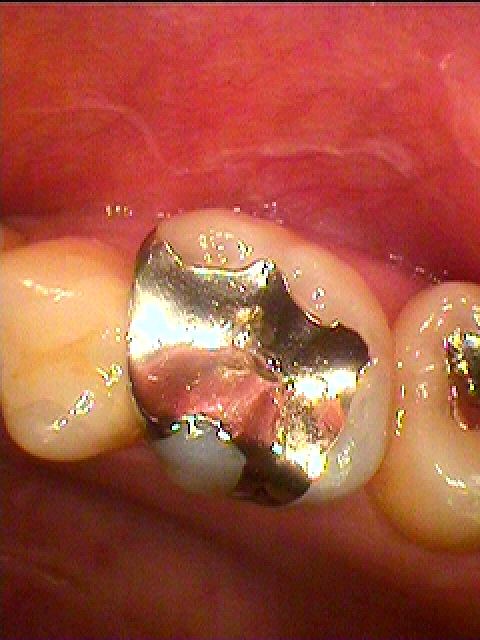

銀歯をすべてセラミックへやり変えていきます セラミックを用いた臨床例 審美治療|お知らせ |広島市安佐南区の歯科医院 銀歯をすべてセラミックへやり変えていきます セラミックを用いた臨床例 審美治療 トップ お知らせ・ブログ お知らせ 銀歯をすべてセラミックへやり変えていきます セラミックを用いた臨床例 審美治療 銀歯をすべてセラミックへやり変えていきます セラミックを用いた臨床例 審美治療 左上の6番部になります この銀歯を外して虫歯治療を行っていきます 中はこのようになっていました 近心部の虫歯を除去していきました CR樹脂にて覆罩を行っています セレックセラミックにて修復しています 銀歯が外れたとのこと わずかに虫歯が存在していました セレックセラミックにて修復しています 綺麗に仕上がりました Web診療予約 初めての方へ 選ばれ続ける理由 院内設備について 歯が痛いしみる一般歯科 歯がぐらぐらする歯周病 健康な歯を保ちたい予防歯科 子供の虫歯予防をしたい小児歯科 銀歯をセラミックに審美歯科 白い歯を目指しませんか?ホワイトニング 矯正専門医がいるので安心矯正歯科 抜けた歯を補いたいインプラント・入れ歯 医院案内 スタッフ紹介 メリィハウス歯科クリニックオフィシャルホームページ ラベンダー歯科クリニックオフィシャルホームページ お知らせ・ブログ ホーム 診療科目 一般歯科 歯周病治療 予防治療 小児歯科 審美治療 ホワイトニング 矯正歯科 入れ歯・インプラント マウスピース矯正 初めての方へ 院長・スタッフ 設備紹介 医院案内・アクセス メニューを閉じる